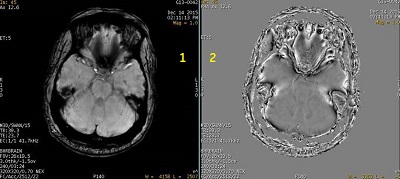

Figure 3. SWAN reformatted and phase images

Table 2. Image legend Number Description 1 SWAN reformatted image that shows area of low signal due to inhomogeneity of anatomy. 2 Reformatted phase image shows non-optimal phase un-wrapping at the inhomogeneous region of anatomy. - When Phase images are generated, a prospective Phase series (described as FILT_PHA) appears in the patient list. For details, Series numbering. Reformatted images can be generated from this series.